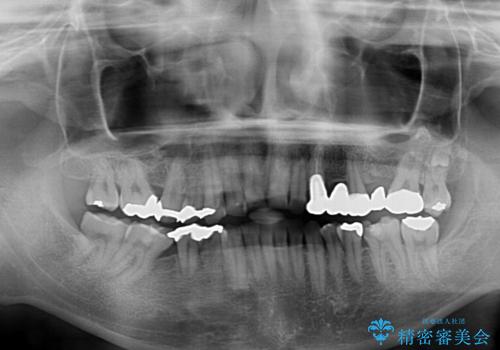

- すり減った前歯や奥歯の銀歯を気にして来院された患者様です。

骨格的な反対咬合により上顎前歯の先端が顕著にすり減っている状態でした。

奥歯の欠損が散見されており、銀歯の装着されている歯も多いため、ワイヤー矯正にて歯列を調整し、その後オールセラミッククラウンにて補綴治療を行うこととしました。

反対咬合改善には奥歯の咬み合わせをしっかりと改善させることが必要となりますが、奥歯に欠損が多いため、矯正治療が難航することが予想されます。